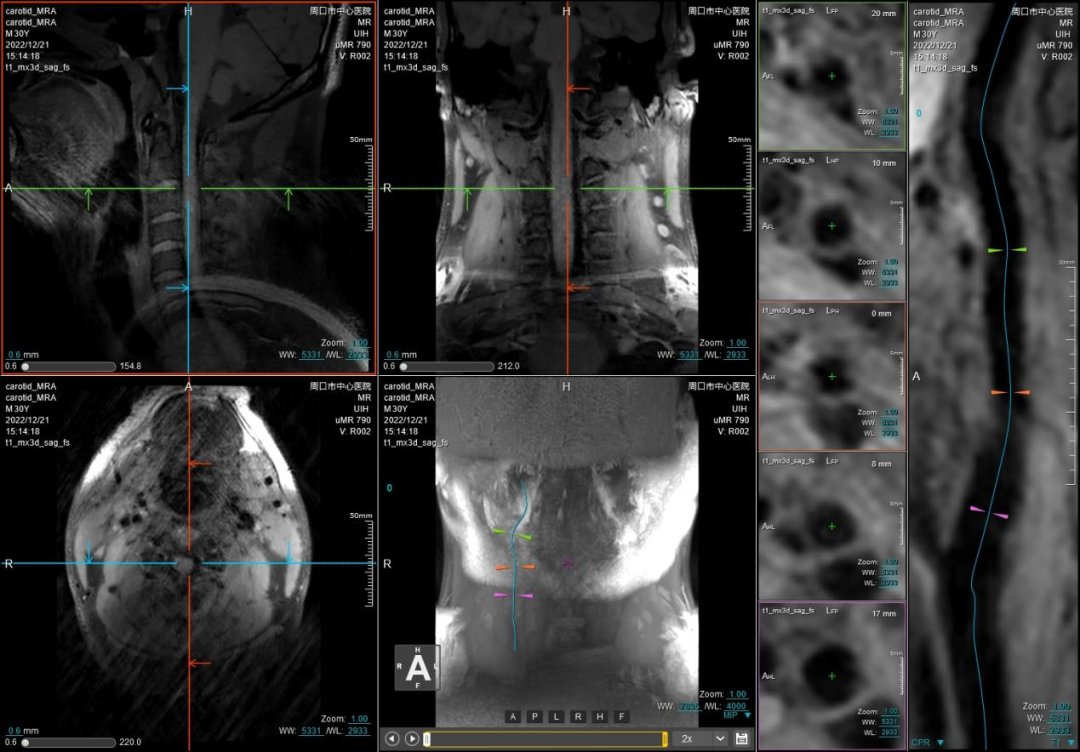

精准!高清晰度磁共振

让颈动脉斑块无处隐藏

最新一代联影光梭uMR790 3.0T 磁共振成像系统不仅可以显示血管狭窄程度、斑块大小和溃疡,还能提供斑块成分、纤维帽厚度和血管壁特征等易损性指标,已成为目前临床识别易损斑块最具有前景的辅助检查手段。

联影磁共振怎么样开启高精度诊断新模式!联影光梭3.0T磁共振落户周口市中心医院_https://www.jmylbn.com_新闻资讯_第5张

周口市中心医院磁共振室现已全面开展各项磁共振高级功能成像(包括SWI、PWI、BOLD、MRS、DTI等)、胎儿、乳腺、心脏、颞颌关节、动脉高分辨血管壁分析以及周围神经等检查,陆续开展磁共振介入和磁共振高级科研临床应用。磁共振功能成像广泛应用于临床各科,如神经内外科、肝胆内外科、心内科、小儿科、妇产科、泌尿科、肿瘤内外科等临床各个学科,这些极其优秀的特色MR成像技术,大大提高临床疑难疾病的诊断符合率,更有助于临床医生更准确有效及时的治疗,让患者得到更优质的康复。比如,DTI用于脑肿瘤对正常白质纤维束的侵占,术前和术后对于治疗效果的评估,可以更准确地反映白质纤维束的空间走向。在心血管领域突破了心脏禁区,可全面评估,心脏大血管解剖结构成像、心肌功能分析等全方位的检查研究,大大方便了中老年心脏病患者。在体部领域实现了肝脏三维容积超快速多期动态增强检查,可以敏感发现早期微小肝癌,不会遗漏边缘部位和微小病变。充分利用GE 3TMR“乳腺微观成像”高分辨展示乳腺结节、导管及淋巴结转移;“磁共振灌注成像”界定急性脑梗塞的缺血半暗带;“波谱成像”能真正在活体(病人)上分析化学成分。因此,努力提升MRS、SWI、DTI、PWI、CEMRA、腹部MR平扫及增强等MR功能成像业务,极大程度地避免了病人要到外地就医问题,也进一步提升了科室技术水平,并能获得良好的社会效益和经济效益。MR引导下穿刺活检及介入治疗。